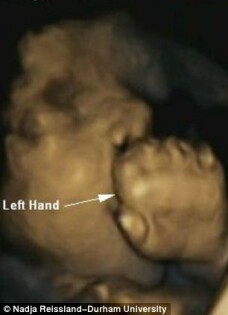

stirileprotv.ro Medicii au aflat ca miscarile pe care le au fetusii in pantecul mamei sunt un bun indicator al sanatatii micutilor, chiar dinainte de nastere.